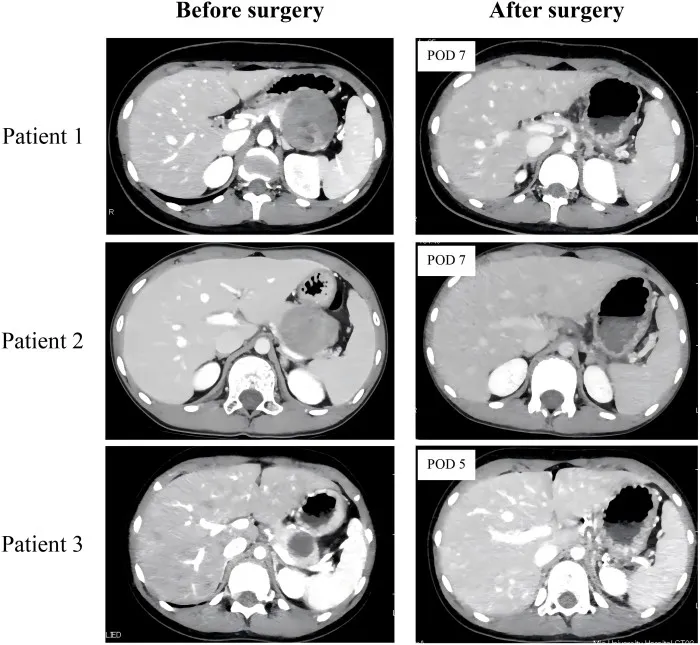

Preoperative and postoperative enhanced computed tomography (CT) findings in three patients undergoing laparoscopic spleen-preserving distal pancreatectomy with Warshaw procedure for solid pseudopapillary neoplasm. The enhanced CT scans verified adequate splenic perfusion, with no notable splenic infarction detected in any cases on postoperative day (POD) 5 or 7.

A significant concern associated with Lap-WT involves postoperative complications, notably splenic infarction and the potential development of perigastric varices, particularly in pediatric cases. Postoperative splenic infarctions were not observed in our study. Initially, the primary collateral supply after splenic vessel resection, as described in the original report of the Warshaw procedure, was thought to be from the short gastric vessels. However, subsequent experimental and clinical investigations identified the left gastroepiploic artery and vein as the primary collateral vessels to the spleen after Warshaw procedure. Hence, it is crucial to dissect the pancreatic parenchyma meticulously from the bifurcation point of the distal splenic vessels encompassing the root of the left gastroepiploic artery at the splenic hilum during Lap-WT. Niec et al. were the first to report two pediatric SPN cases who underwent Lap-WT, with a median follow-up of 23 months after surgery, worldwide. Their surgical procedure emphasized the crucial importance of preserving the vasa brevia, specifically short gastric vessels, to maintain spleen perfusion. However, in their case series, both patients were reported to develop postoperative central splenic infarction, with postoperative CT scans showing a reduction in spleen volume of 65% and 74% compared with the preoperative volume, likely due to splenic atrophy resulting from focal splenic infarction. In Lap-WT, our tail-first approach prioritizes meticulous dissection of the pancreatic tail parenchyma from the splenic hilum to precisely isolate distal splenic vessels during the initial surgical stages. This technique facilitates the preservation of both roots of the left gastroepiploic artery and the short gastric artery, enabling a more precise stapler division of the distal splenic vessels. To the best of our knowledge, this is the first report of Lap-WT in pediatric patients where splenic perfusion was successfully maintained without any occurrence of splenic infarction, as confirmed by postoperative CT scans.